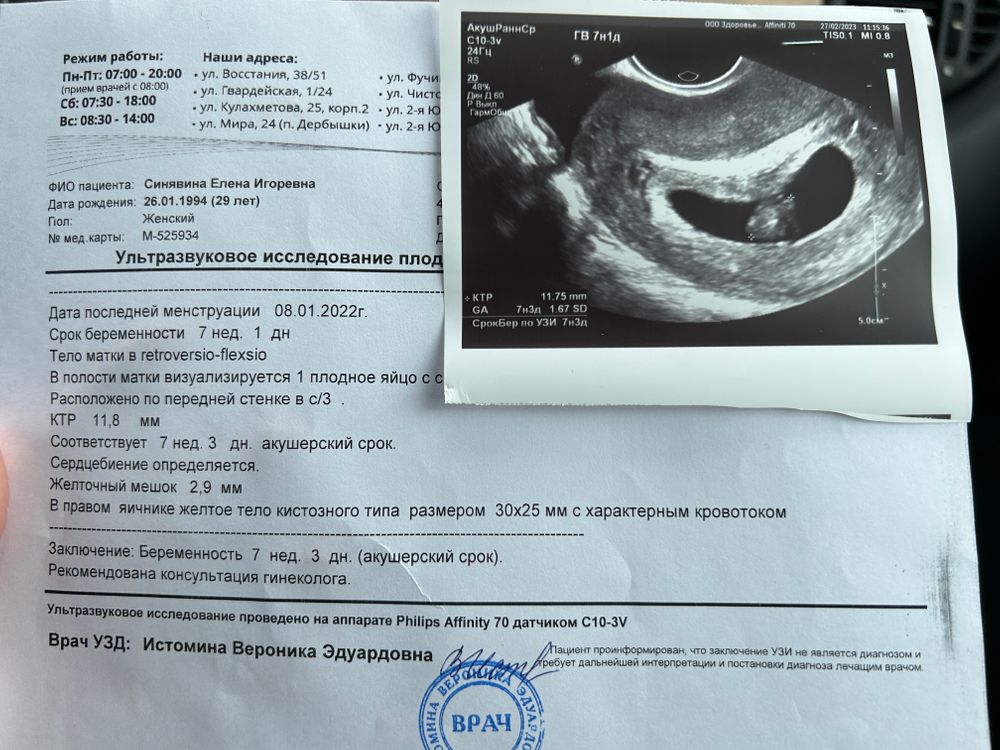

Фотографии на ранних этапах беременности

Раздел: Визуальный дайджест